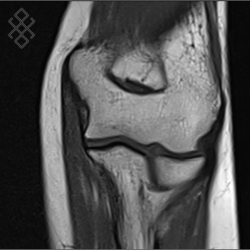

IRM du Coude

Vous entrez dans l'aimant, ouvert des 2 côtés, la tête la première et allongé sur le dos avec les bras le long du corps. Pour recueillir le signal et construire les images, vous aurez le coude dans une antenne. Étant donné que cet examen est bruyant, vous aurez à votre disposition des tampons auriculaires pour atténuer le bruit de la machine.